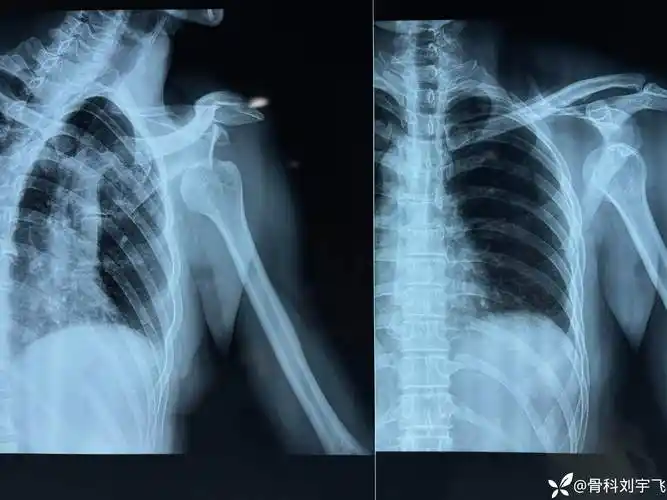

肩关节脱位那些事儿(七)—少见的双侧肩关节脱位